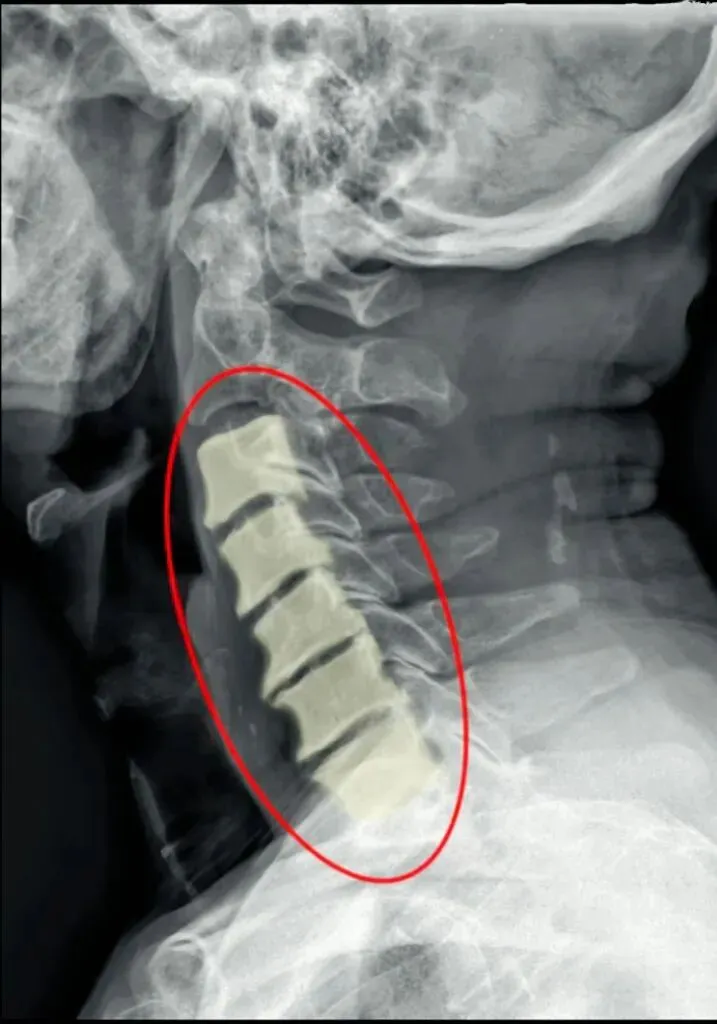

五间是指颈椎椎间隙的变化,主要在颈椎侧位片上观察椎间隙变化同时也反映了椎间盘的变化。

颈椎的退变最早发生在C56椎间盘上,因此C56椎间隙也最早发现变窄的征象。

颈椎骨性椎体为前低后高,

而椎间盘则为前高后低,因此颈椎的生理性前凸是由椎间盘的前高后低所形成的。

在正常情况下,C23、C34和C45间隙大致相等,椎间隙前部为3.8毫米正负0.5毫米,

后缘间隙为1.9毫米正负0.28毫米。

C56间隙较上为宽,而C67间隙最宽,但C7与T1间隙又较窄。